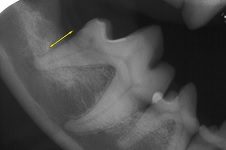

Periodontal Pocket May 2009-03

The yellow arrow on the radiograph indicates the localized area of boneloss called a periodontal pocket.